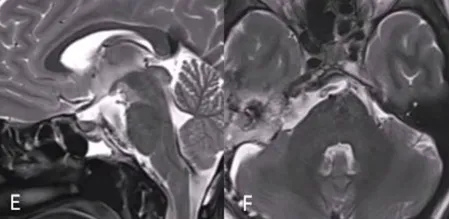

26岁女性,阵发性复视,进行性左外展神经麻痹,MRI显示斜坡巨大脊索瘤,病变浸润性生长,肿瘤延伸浸润至乙状窦(SS)、左侧海绵窦(CS)、下斜坡到脑干脚间池硬膜部分(图A、B)。

首先,进行内镜鼻内活检,显示典型的脊索瘤。然后,她接受了内镜经鼻入路手术,从硬膜外部分切除到斜坡和海绵窦部分的肿瘤(图C、D)。

2个月后,进行第二次手术,使用右侧mini经岩骨入路切除硬膜内肿瘤。术后MRI显示肿瘤完全切除GTR(图E、F)。术后接受了质子束治疗(PBT)。5个月随访时,她的神经系统检查正常,头面部外观美容效果也非常好。